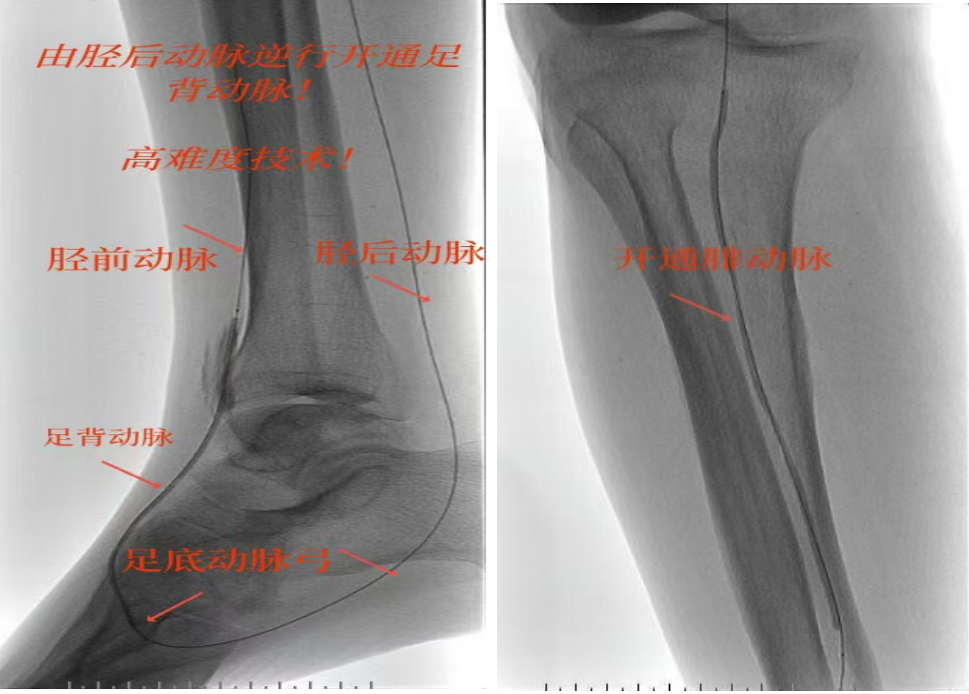

78岁男性患者,糖尿病合并高血压、脑梗塞,右足持续疼痛伴冰凉发绀3个月。入院CTA显示其右侧股浅动脉全程闭塞,膝下三支动脉均闭塞。医疗团队在局部麻醉下,再次巧妙应用“逆向开通技术”,经胫后动脉——足底弓逆向开通足背动脉及胫前动脉。术后患者右足皮温即刻回升,疼痛消失。术后结合中药外治(换药、熏洗、去腐生肌膏外敷)加速创面愈合,患者已顺利出院。

影像检查:CTA显示右侧股浅动脉全程闭塞,膝下三支动脉(胫前、胫后、腓动脉)完全闭塞。